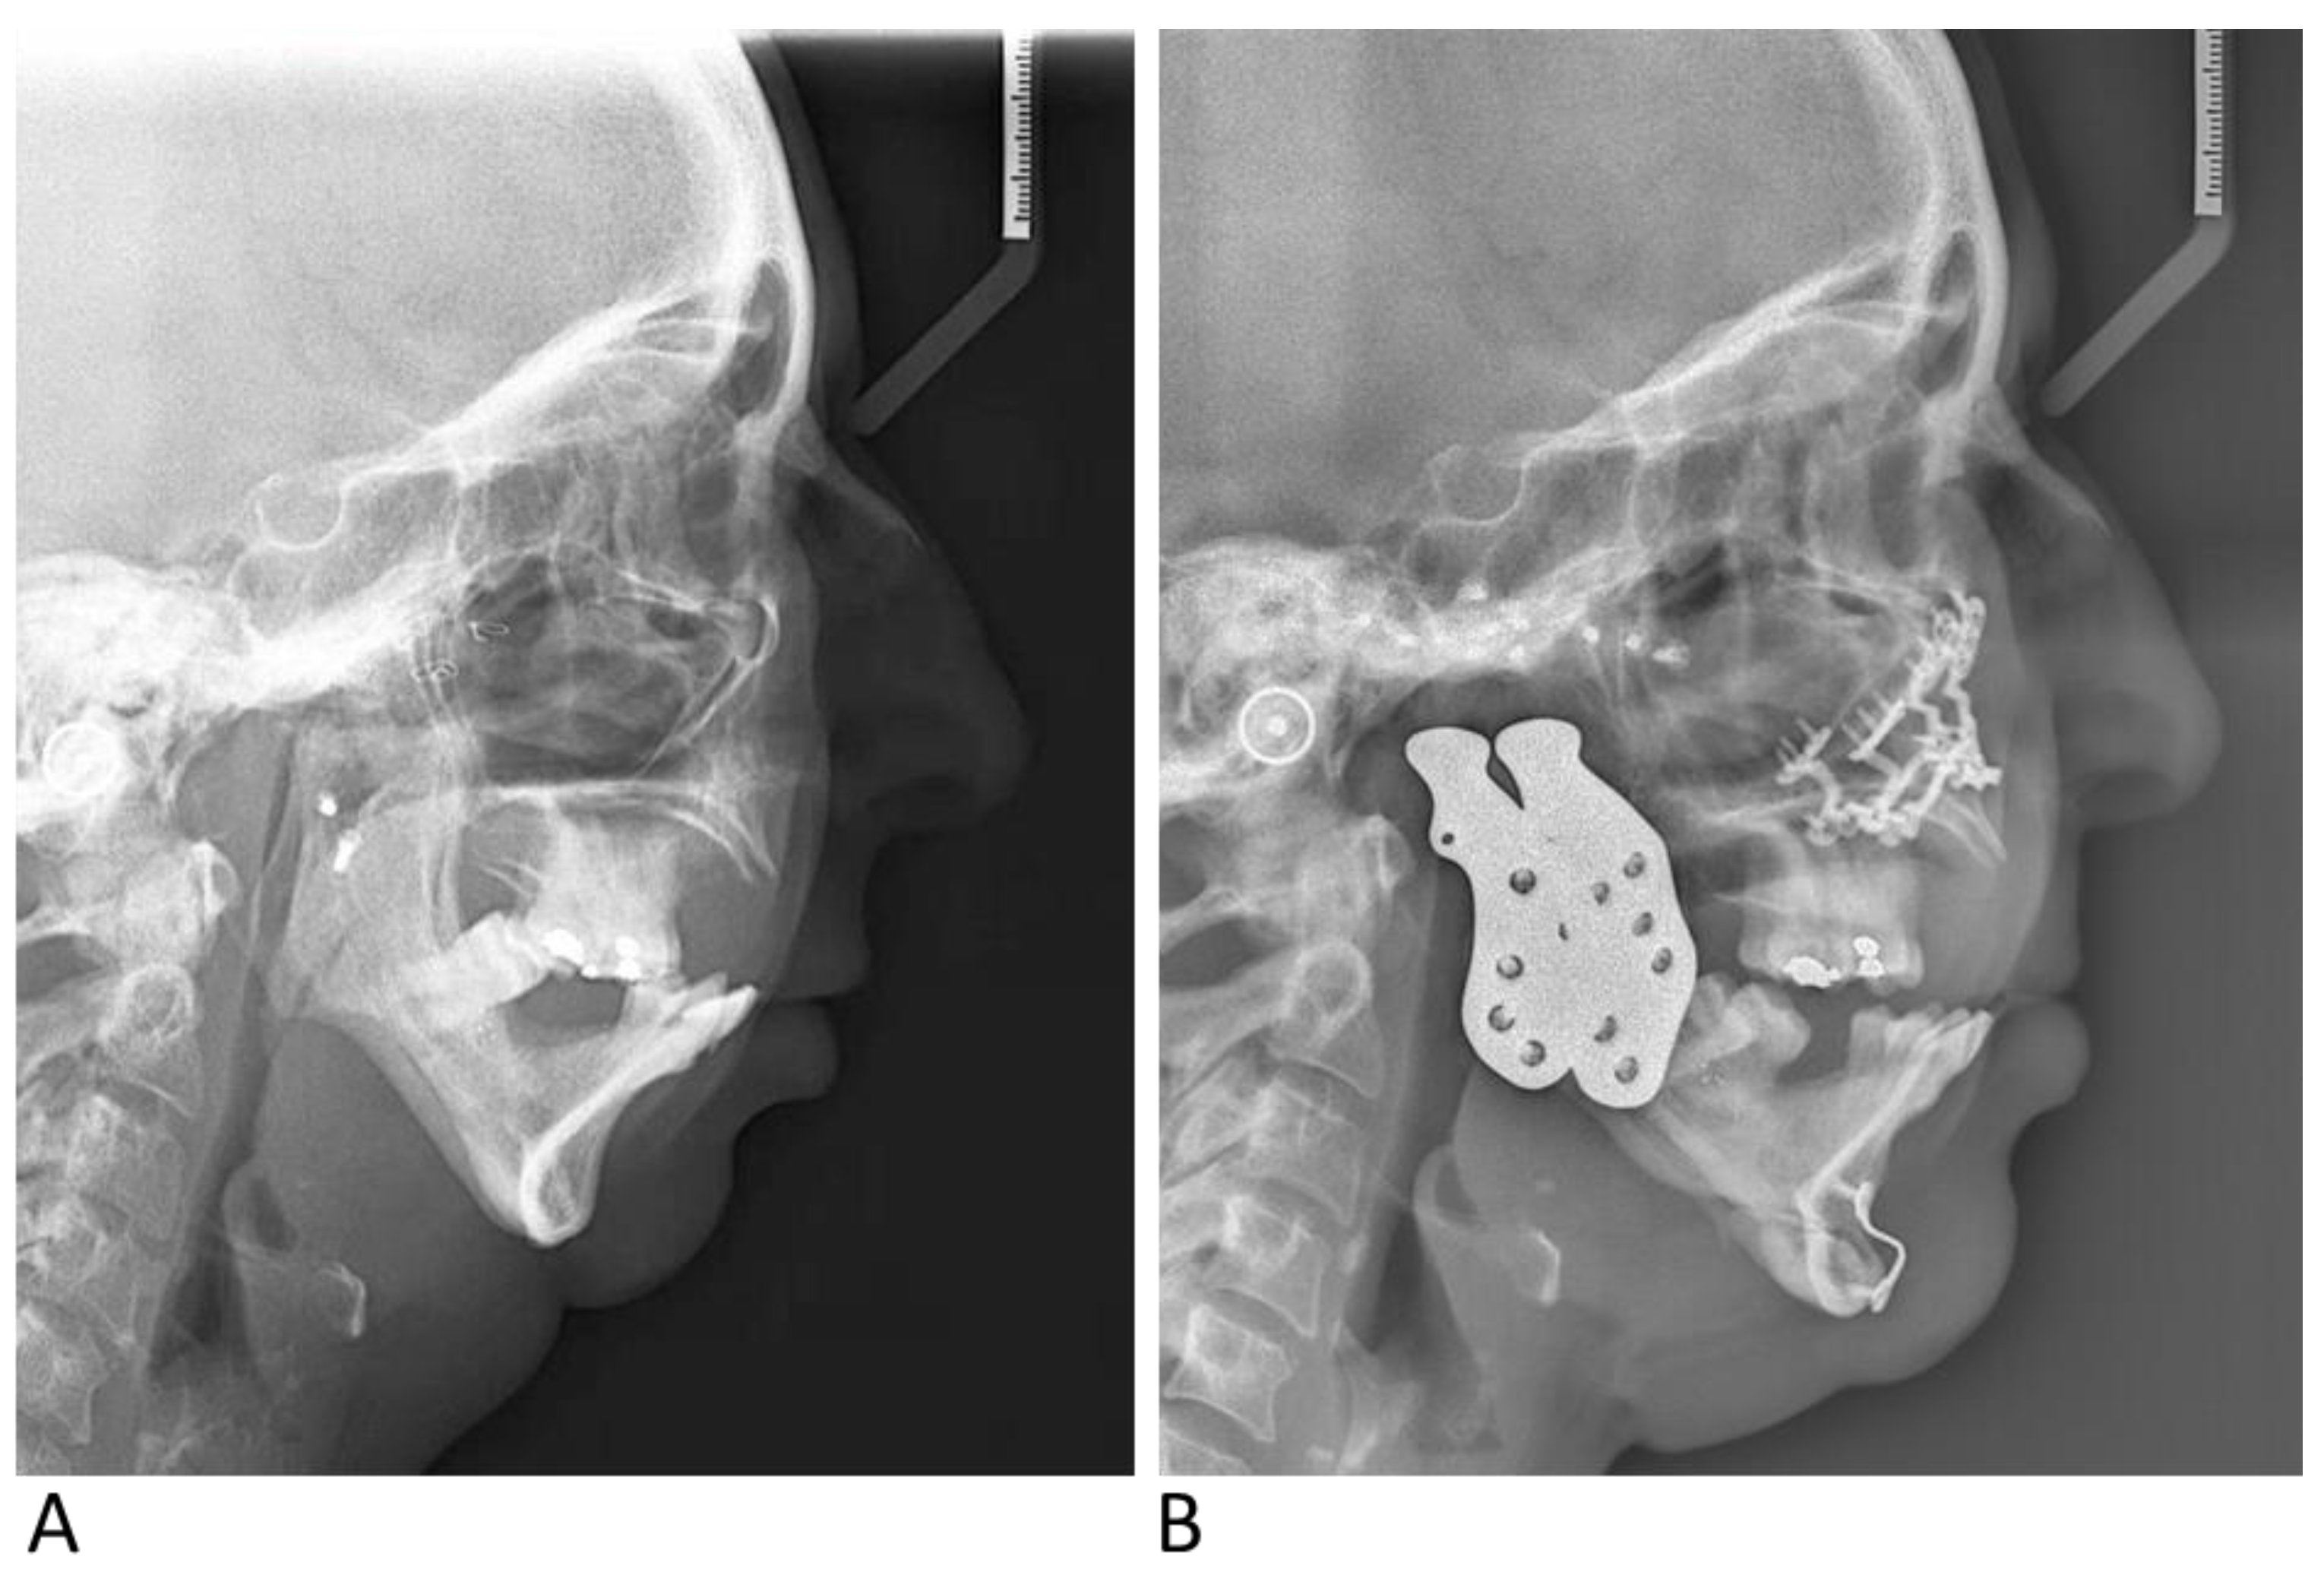

3. Case Report

3.1. Case 1

3.2. Case 2

3.3. Case 3